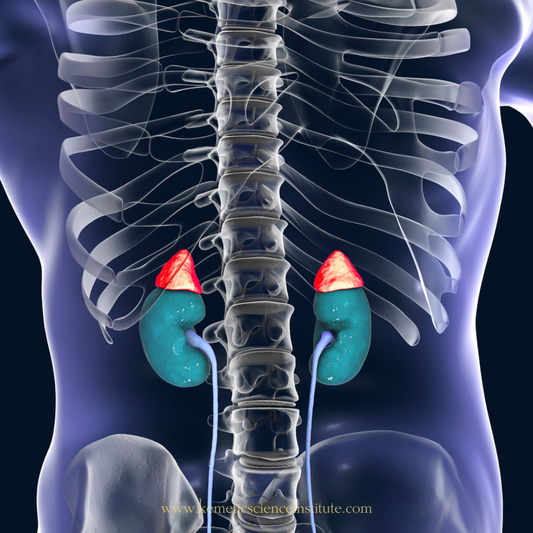

The Kidneys' Connection to Optimal Health

We know the general functions of our heart, lungs, stomach, etc., but do you truly realize how important your kidneys are and why? Every organ plays a crucial role in...

The Kidneys' Connection to Optimal Health

We know the general functions of our heart, lungs, stomach, etc., but do you truly realize how important your kidneys are and why? Every organ plays a crucial role in...